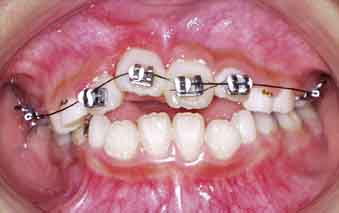

初診の状態